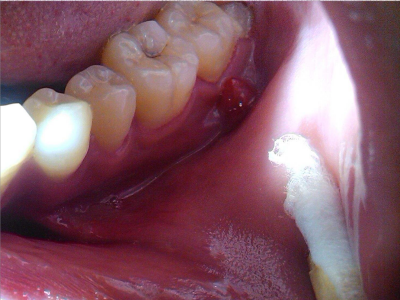

智齿冠周炎右下方的牙龈最内侧红肿图

智齿冠周炎患者右下方的牙龈最内侧有红肿,红肿处有一小创口,可见其内的牙齿,牙齿未完整露出,小创口边缘微微发白,患者自觉有明显疼痛。